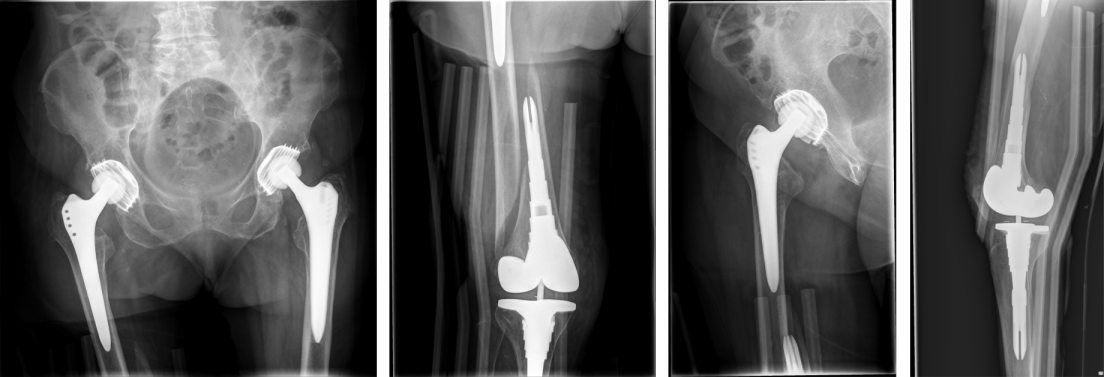

The surgical procedure for subtotal replacement of the femoral diaphysis was performed without any intra- or postoperative complication. The duration for the surgical intervention was one hour and 40 minutes. The patient was then mobilized with full weight bearing supervised by physiotherapists at ward level, which she tolerated well. The pain was significantly relieved during hospital stay. The postoperative radiographs showed correct implant position and a satisfactory surgical result (Figure 6 [Fig. 6]).

Figure 6: The postoperative radiographs showed correct implant.

At one-year follow-up, the patient did not complain of any pain. The Harris Hip Score HHS improved from 26 (prior to partial diaphyseal replacement) to 83 at one-year follow-up (Figure 7 [Fig. 7]), the Western Ontario and McMaster Universities Osteoarthritis Index WOMAC improved from 88 to 16. The range of motion of the right hip joint one year after surgery was: extension/flexion 0/0/90°, abduction/adduction 30/0/20°, external rotation/internal rotation 30/0/20°. The range of motion of the right knee joint one year after surgery was: extension/flexion: 0/0/120°. There were no symptoms or signs of infection or any other complications.

Figure 7: Postoperative radiographs one year after surgery without any morphological changes compared to postoperative radiographs